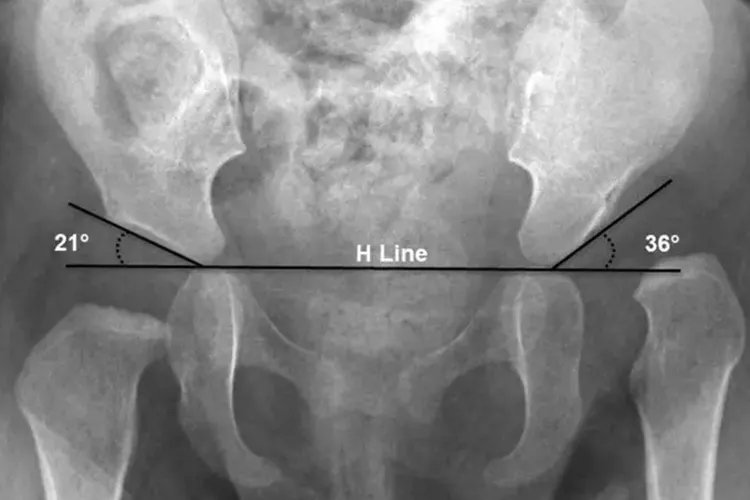

左右胯骨不对称图片

的有关信息介绍如下:概述胯骨即髋骨,左右髋骨不对称可表现为髋关节屈曲、内收、内旋,或一侧髋骨倾斜、突出。髋关节疾病,如髋关节脱位、髋关节发育不良和腰椎间盘突出等可能导致左右髋骨不对称。症状左右髋骨不对称可能由髋关节脱位、髋关节发育不良或者腰椎间盘突出导致,具体症状如下:髋关节脱位髋关节后脱位较为常见,表现为髋关节疼痛和活动障碍。患肢短缩,髋关节呈屈曲、内收、内旋畸形。可以在臀部摸到脱出的股骨头,大转子上移明显。髋关节后脱位可合并坐骨神经损伤,从而出现足下垂、趾背伸无力和足背外侧感觉障碍等。

髋关节发育不良儿童可出现两下肢长短不一,且患侧下肢活动力较差;患肢髋关节较不易向外展开;两侧大腿内侧、腹股沟、会阴部或臀部之皮肤皱褶不对称;患侧的大腿粗隆向上外凸起。

腰椎间盘突出表现为腰痛、坐骨神经痛、大小便障碍和鞍区感觉异常等。患者为了减轻疼痛,会出现姿势性代偿畸形,表现为腰椎侧凸、两侧髋骨不对称等。